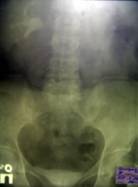

Контрольное обследование, произведенное в апреле 2006 года (через 12 месяцев после нефрэктомии и, соответственно, через 7 месяцев после пластики рецидивного ПВС), не обнаружило признаков рецидива онкопроцесса. При вагинальном осмотре определяется опущение передней стенки влагалища, на нисходящей урограмме - опущение мочевого пузыря (Рис. 3). Жалобы на какое-либо нарушение акта мочеиспускания отсутствуют. В общем анализе крови: содержание гемоглобина - 150 г/л, СОЭ - 4 мм/час. Впервые выявлен сахарный диабет.

Выделительная урограмма с нисходящей цистограммой

Рис. 3. Выделительная урограмма с нисходящей цистограммой.